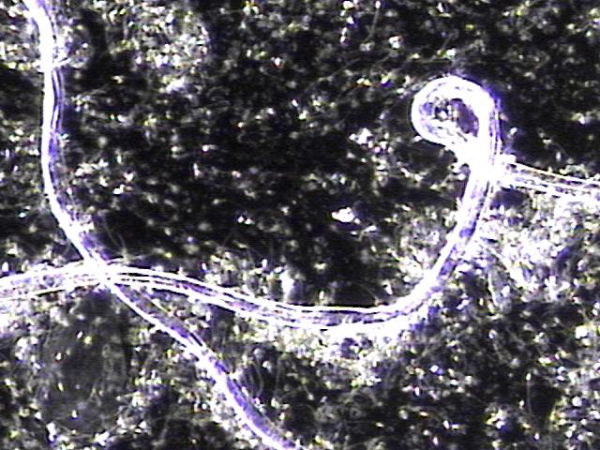

주 2회 전립선과 정낭 그리고 정관등의 표적 치료중 정관을 막고 있는 거짓중층원주상피세포와 사정되지 못한 정자들과 단백질등의 치료된 현미경학적 자료입니다.

This microscopic image was taken after repeated targeted treatment.

It shows that old cells, proteins, and sperm had collected and blocked the vas deferens.

The size of this material confirms that it was stuck inside the vas deferens.

The treatment helped to remove this blockage, allowing the ducts to open and improving the flow of semen.

사진 속 현미경 영상은 정관에서 배출된 치료 후 내용물로 보입니다. 관찰되는 소견을 근거로 말씀드리면:

-

길게 뻗은 섬유성 구조와 세포성 잔여물이 함께 보입니다.

이는 흔히 노화된 거짓중층원주상피세포, 단백질 덩어리, 또는 정자와 점액질이 엉겨 붙은 물질일 가능성이 높습니다.

직경이 비교적 크고 길게 뭉친 형태를 띠기 때문에, 정관 내강을 막아 정액의 흐름을 방해했을 것으로 추정됩니다.

즉, 정관을 막고 있던 주된 원인은

오래된 상피세포 찌꺼기, 단백질 응집물, 그리고 사정되지 못하고 고여 있던 정자들이 엉겨 형성된 덩어리(blockage material) 로 보입니다.

This microscopic image shows material that was removed after targeted treatment of the vas deferens.

The findings suggest that the blockage was mainly caused by:

- Old cells that had shed from the lining,

- Protein debris, and

- Sperm that could not be released and became trapped.

These substances clumped together over time and formed a plug large enough to block the vas deferens, preventing normal flow.

The treatment helped clear this material, allowing for better passage through the duct.